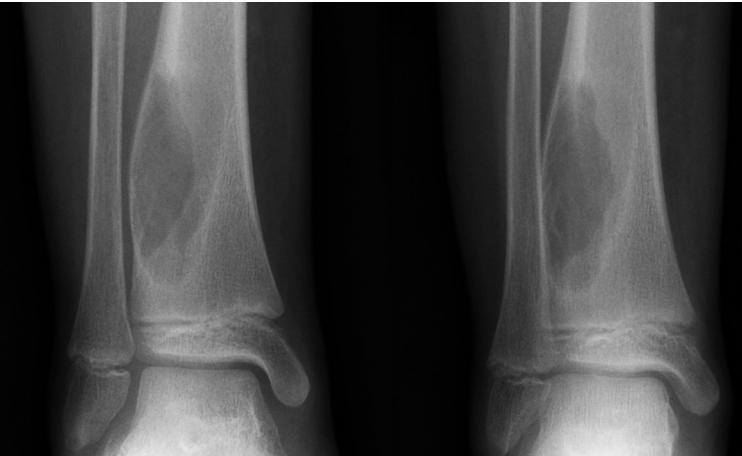

Non-Ossifying Fibroma

- Another name: Fibrous cortical defect

- The commonest benign lesion of bone

- Asymptomatic:

- Incidentally discovered

- Children:

- Disappears later

- Common site:

- Metaphysis of long bones

- Treatment:

- Observation

- Surgery if very large

Non-ossifying fibroma …Fibrous cortical defect